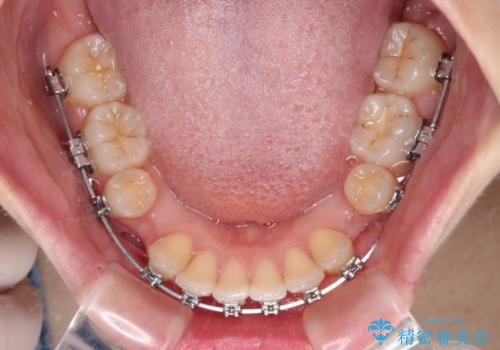

- 上下の前歯が突出しており、口が閉じにくいとのことで来院された患者様です。

上下前歯が著しく前突している状態であったので、上下左右の第1小臼歯4本を抜歯し、ワイヤー装置にて矯正治療を行うこととしました。

舌の突出癖により、前突になったと考えられたため、舌のトレーニングをしっかりと行うよう指導しました。

※写真にある上顎装置はメタルブラケットではありません。メーカー在庫都合などにより別の装置を使用しております。